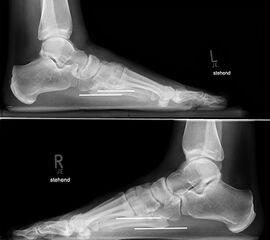

Standardisierte Röntgenaufnahmen des betroffenen Fußes, dorsoplantar (dp), streng seitlich sowie eine Schrägaufnahme werden angefertigt. Diese sollten möglichst unter Belastung angefertigt werden, da in den unbelasteten Aufnahmen insbesondere diskrete Veränderungen häufig nicht sicher zu erkennen sind.

Auf den dp-Aufnahmen sollte der mediale Rand der Metatarsale-2-Basis mit dem medialen Rand des Os cuneiforme intermedium eine homogene Linie ohne Stufenbildung bilden (Abb. 7+8). Außerdem ist auf den Abstand zwischen der Metatarsale-1- und -2-Basis zu achten. Dieser sollte nicht größer als 2 mm bzw. im Vergleich zur Gegenseite nicht mehr als 1 mm erweitert sein. In bis zu 90% der Fälle zeigt sich ein sogenanntes „Fleck sign“ (Abb. 9), ein knöchernes Fragment zwischen der Metararsale-1- und -2-Basis im Sinne eines knöchernen Ausrisses des Lisfranc-Ligaments an der Metatarsale-2-Basis 211936410. Oft liegen zusätzliche Frakturen der Metatarsalebasen oder der Tarsale vor, die ebenfalls identifiziert werden sollten. Bei jeder Mittelfußbasisfraktur sollte umgekehrt an eine Lisfranc-Verletzung gedacht werden.

Zum Lesen der Bildbeschreibung und zur Vollansicht bitte die Bilder anklicken.

In der Schrägaufnahme sollte der mediale Rand des Cuboids mit dem medialen Rand der Metatarsale-4-Basis eine homogene Linie bilden.

In der seitlichen Aufnahme ist auf Dislokationen und Subluxationen in den Tarsometatarsalgelenken sowie auf einen Verlust des Fußlängsgewölbes zu achten. Bei Instabilitäten des 1. Strahls bzw. Abflachung des Fußlängsgewölbes tritt in der Seitaufnahme die plantare Kontur des Os cuneiforme mediale tiefer im Vergleich zur Basis des Metatarsale 5. Darüber hinaus sollte die Cyma-Linie im Bereich des Chopartgelenkes in der Seitaufnahme eine harmonische S-förmige Linie bilden.

Insbesondere bei rein ligamentären, aber auch subtilen Verletzungen können belastete Vergleichsaufnahmen der unverletzten Gegenseite oder Streßaufnahmen des verletzten Fußes unter Bildwandlerkontrolle hilfreich sein 161129584 (Richter 2007).

Aber auch in den belasteten Röntgenaufnahmen sind subtile Frakturen und Luxationen oder rein ligamentäre Verletzungen oft nicht sicher darstellbar 7.

Zum Lesen der Bildbeschreibung und zur Vollansicht bitte das Bild anklicken.